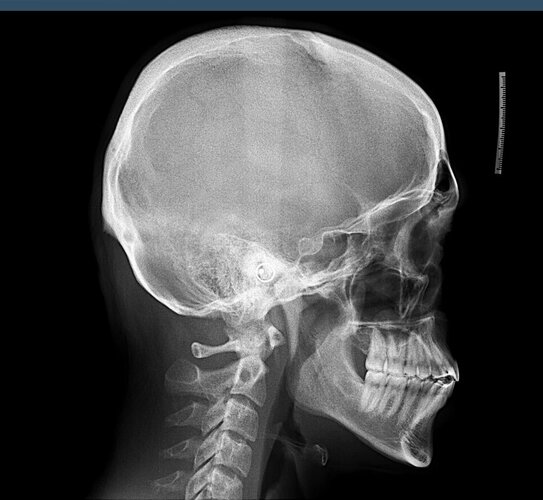

Is it possible to fix my lower jaw recession with orthodontics (braces etc) or only brutal hardmax is the way here? I don’t see a significant lack of upper jaw projection of bone mass problem, it looks like the problem is my teeth (especially my front teeth that make my mouth look monkey like), but I don’t see how they can be positioned in order to rotate my lower jaw in a clockwise direction. Feel free to express yall opinion!!!